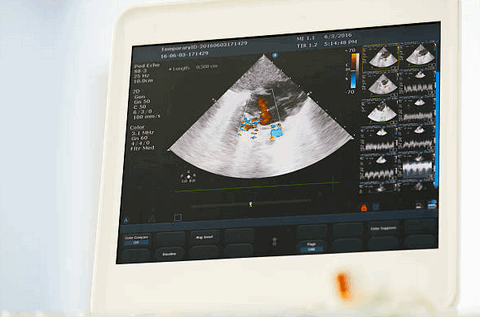

Заболевания сердечно-сосудистой системы являются самыми частыми в процентной структуре болезней. Это основная причина смерти и потери трудоспособности во всем мире. Люди, которые подвержены высокому риску таких патологий, обязательно должны проходить прицельное медицинское обследование для раннего выявления и предупреждения осложнений. К одной из таких процедур относится эхокардиография сердца. Это метод ультразвукового исследования, который позволяет оценить работу сердца и его клапанного аппарата, своевременно диагностировать какие-либо изменения.

Точность результатов исследования зависит и от разрешения прибора. Современный аппарат УЗИ должен быть снабжен функцией «допплерограф». Это даёт больше информации о кровотоке внутри того или иного сосуда, что крайне важно для диагностики внутриутробного развития.

ЭхоКГ не позволяет отличить доброкачественные опухоли от злокачественных. 2-D эхокардиография показывает опухоли как эхогенные образования в полости сердца, прикрепленные к стенке или находящиеся в перикарде. Обычно их размер и мобильность можно хорошо определить. Как и во всех исследованиях при проведении ЭхоКГ, необходимо получить несколько изображений. Иногда в M-режиме можно увидеть опухоль, такую как миксома, нарушающая функцию клапана. Эффекты опухолей (например, обструкция клапана, дисфункция ЛЖ из-за инфильтрации, обструкции или перикардиального выпота) также можно увидеть на эхокардиографии.